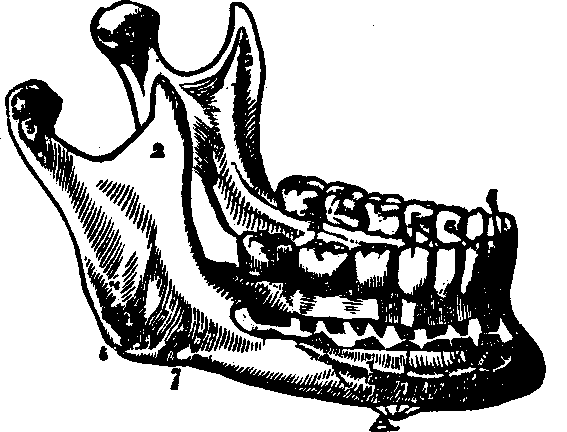

Fig. 26. A view of the lower jaw. 1. The body. 2, 2. Rami,

or branches. 3, 3. Processes of the lower jaw. m. Molar

teeth. b. Bicuspids, c. Cuspids. i. Incisors.

The Teeth are firmly inserted in the alveoli or sockets, of the upper and the lower jaw. The first set, twenty in number, are temporary, and appear during infancy. They are replaced [pg 38]by permanent teeth, of which there are sixteen in each jaw; four incisors, or front teeth, four cuspids, or eye teeth, four bicuspids, or grinders, and four molars, or large grinders. Each tooth is divided into the crown, body, and root. The crown is the grinding surface; the body, the part projecting from the jaw, is the seat of sensation and nutrition; the root is that portion of the tooth which is inserted in the alveolus. The teeth are composed of dentine, or ivory, and enamel. The ivory forms the greater portion of the body and root, while the enamel covers the exposed surface. The small white cords communicating with the teeth are the nerves.